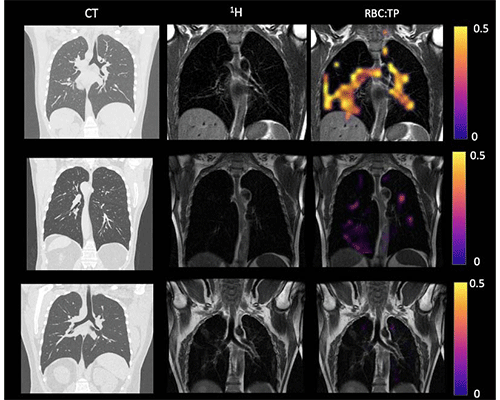

Example CT, proton, proton and RBC:TP imaging from post-hospitalized participants. The top row is a participant with RBC:TP = 0.59, the middle row is a participant with RBC:TP of 0.31, and the bottom row is a participant with RBC:TP = 0.16. Imaging showed minimal damage on CT, and yet highly heterogeneous and low RBC:TP in the lungs of post-hospitalized participants. RBC:TP = Hyperpolarized 129Xenon MRI lung ratio of red blood cell spectral peak to tissue phase spectral peak

Grist et al, Radiology in Press 2022 © RSNA 2022